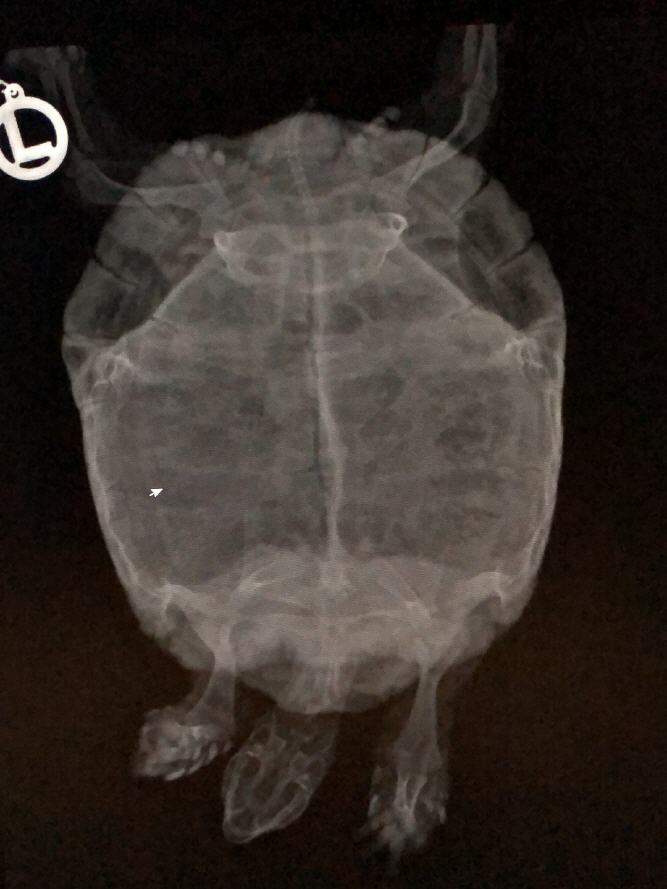

Patientengalerie

Wundversorgung bei einem Steinadler